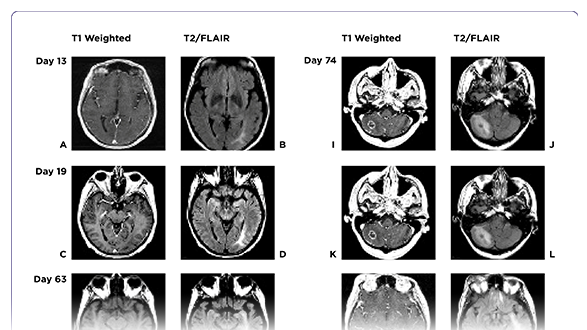

Metastatic Melanoma With Leptomeningeal Disease

Amanda M. Marinova, MS, PA-C, Jennifer L. Reilly, CRNP, BSN, MSN, RN, AANP, Victoria Wong, MS, PA-C, Stephanie Weiss, MD, and Anthony J. Olszanski, MD

January 19, 2021